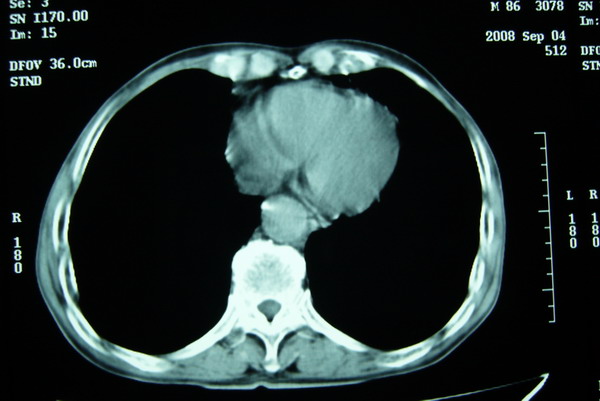

标题: CT15579:男 86岁 咳嗽 咳少量白痰 发热2天 吸烟史60年 [打印本页]

标题: CT15579:男 86岁 咳嗽 咳少量白痰 发热2天 吸烟史60年

右肺上叶巨大软组织肿块,轮廓不规则,纵隔内有肿大淋巴结,首先考虑肺癌。

右上肺一不规则团块,边缘有分叶和毛刺,纵隔有淋巴结肿大。右肺周围性肺癌首先考虑。